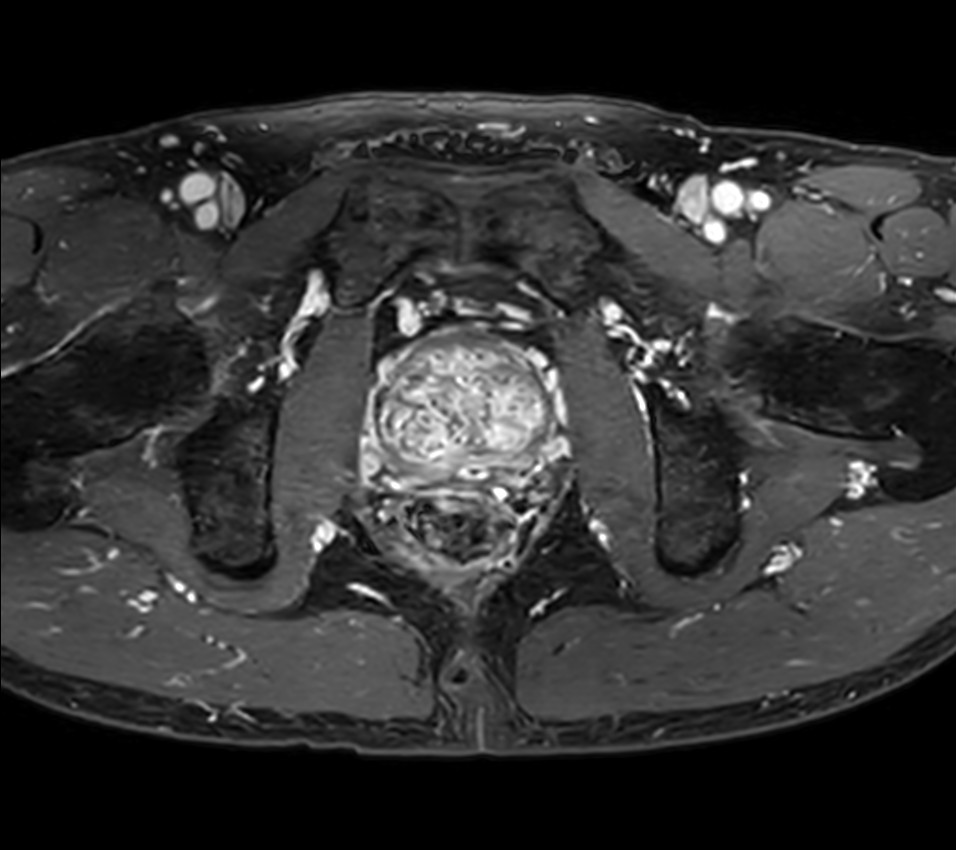

Fast Prostate imaging with SmartSpeed Precise

Kumamoto Chuo Hospital Japan

Used Solution